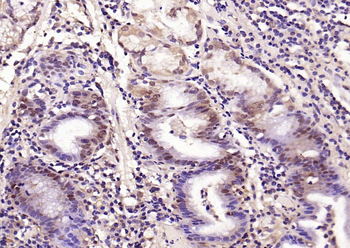

Phospho-Smad3 (Ser423 + Ser425) Rabbit Polyclonal Antibody [orb6983]

FC, IF, IHC-Fr, IHC-P, WB

Bovine, Canine, Equine, Gallus

Human, Mouse, Porcine, Rat

Rabbit

Polyclonal

Unconjugated

100 μl, 200 μl, 50 μlSMAD7 Rabbit Polyclonal Antibody [orb500819]

FC, ICC, IF, IHC-Fr, IHC-P, WB

Bovine, Porcine

Human, Mouse, Rat

Rabbit

Polyclonal

Unconjugated

100 μl, 200 μl, 50 μlPhospho-Smad3 (Ser213) Rabbit Polyclonal Antibody [orb106193]